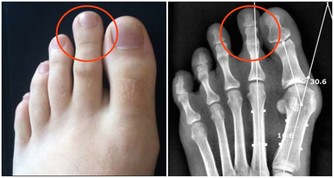

1 、幫你的關節“減負”

你肯定不知道你的關節每天在承受多大的力量,體重每增加1%,關節的承重就會增加4%,我們經常看到很多上了歲數的老年人,走起路來顫顫巍巍,腿都伸不直,可能就是因為在年輕時沒有好好愛護自己的關節,使得關節的使用壽命大大下降了。